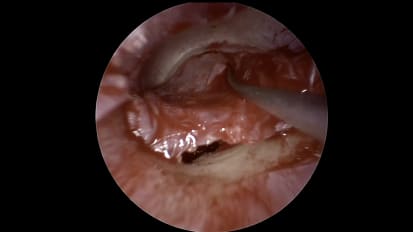

Mount Sinai head and neck surgeons perform a direct laryngoscopy with biopsy of the tongue base to confirm a diagnosis of squamous cell carcinomaMount Sinai Otolaryngology Surgical Series: Ear Drum Repair (Tympanoplasty) With Lateral Graft

Mount Sinai neurotologists perform a minimally invasive endoscopic approach to perform a lateral graft tympanoplastyMount Sinai Otolaryngology Surgical Series: Ear Tube Placement (Myringotomy)